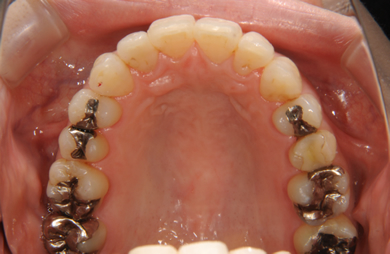

| 性別/年齢 | 女性 / 31歳 | ||||||||||||||||||||||||||||||||

| 主訴 | 歯並びを綺麗にしたい。 | ||||||||||||||||||||||||||||||||

| 治療方針 | 口元がきれいなので、なるべく横顔を変えないように歯を抜かずに治療を行う。しかし、下顎がだいぶ前に出ていて、上下の顎の前後的な位置のずれが大きいため、下顎にはインプラントアンカーを用いて、下の歯を本来の位置まで後ろに引っ張って治す。 | ||||||||||||||||||||||||||||||||

| 治療内容 | 唇側矯正(シルバー)、保定装置、矯正用スピードインプラント2本 | ||||||||||||||||||||||||||||||||

| 治療期間 | 1年5ヶ月 |